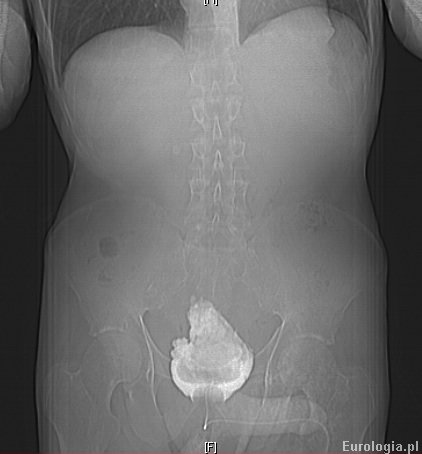

W wykonanym badaniu tomografii komputerowej jamy brzusznej stwierdzono duży złóg wypełniający w całości światlo pęcherza moczowego. W 22 dobie hospitalizacji pacjenta wydolnego krążeniowo - odedechowo z dobrymi parametrami nerkowymi przekazano do oddziału urologicznego celem leczenia przyczynowego. Ze względu na duży rozmiar zlogu zdecydowano o wykonaniu klasycznej operacji usunięcia złogu z pęcherza moczowego.